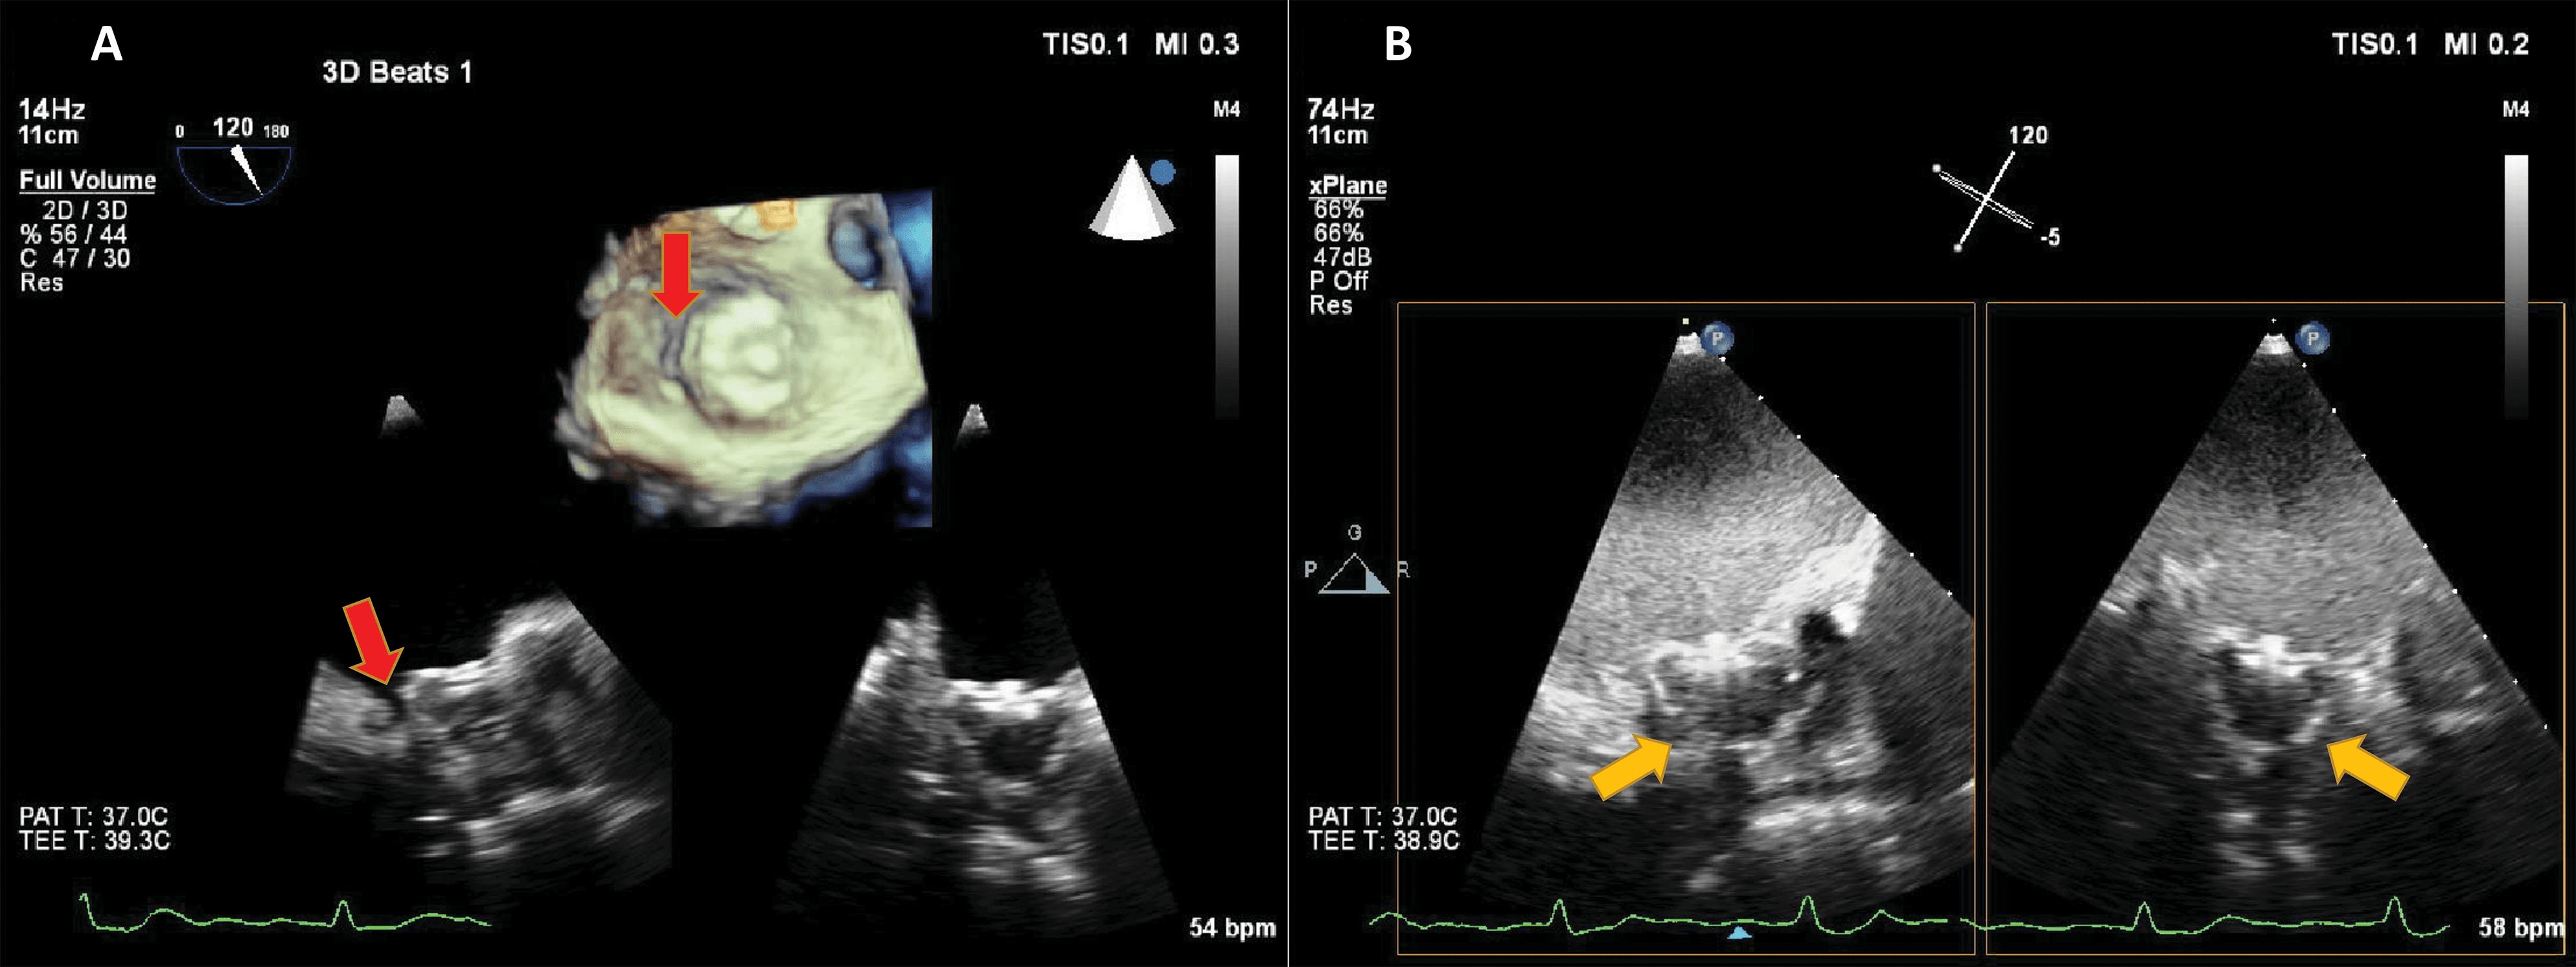

However, contrast-specific transoesophageal applications are not available on all ultrasound clinical systems, therefore in such cases non-contrast mode harmonic 2D imaging may be used, with a mechanical index (MI) under 0.3 (Fig. 6, Video 5).

Fig. 6.Transoesophageal echocardiography in a patient with a Watchman left atrial appendage (LAA) closure device. Microbubble-enhanced ultrasound was used in order to detect a suspected residual leak around the occluder. On non-enhanced multiplane and live 3D images (A) a gap is visible (red arrows) between the rim of the device and the LAA. Because of shadowing, the sealing of the LAA cannot be verified. By adding intravenous contrast (B) and using harmonic imaging with a mechanical index of 0.2, contrast is seen in the LAA, surrounding the device (yellow arrows), demonstrating incomplete sealing of the LAA. Source: personal collection.